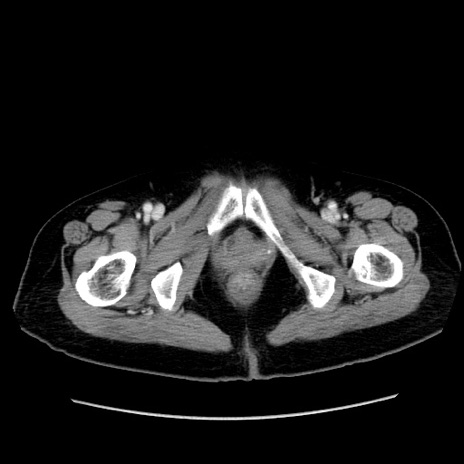

症例19(横断像)

【症例】80歳代女性

【主訴】下腹部痛

【現病歴】約8時間前より下腹部痛の出現あり、救急外来受診。

【既往歴】両側付属器切除

【身体所見】意識清明、下腹部正中に手術痕あり、その部位に一致して圧痛と反跳痛あり。腸蠕動音は亢進。

【データ】WBC 9300、CRP 0.15